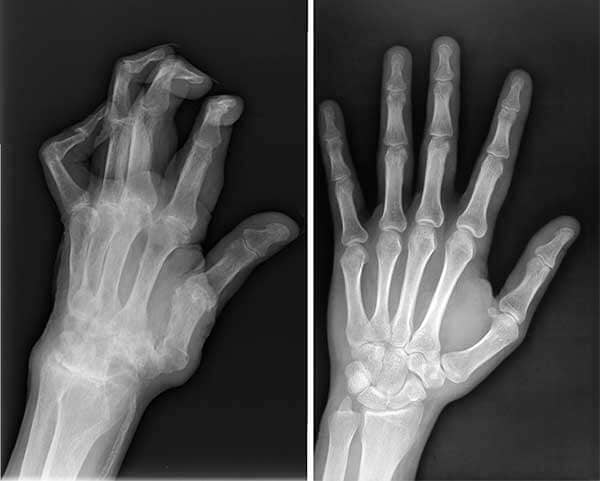

Imagen 12

Radiografías de las manos de Carlos, antes y después de Flexacil.

Incluso mi esposo, Carlos, padecía artritis en los dedos. Sus manos se deformaban y a veces el dolor era insoportable. No podía ni sostener una taza de café. Le di Flexacil, y ahora vive sin dolor.